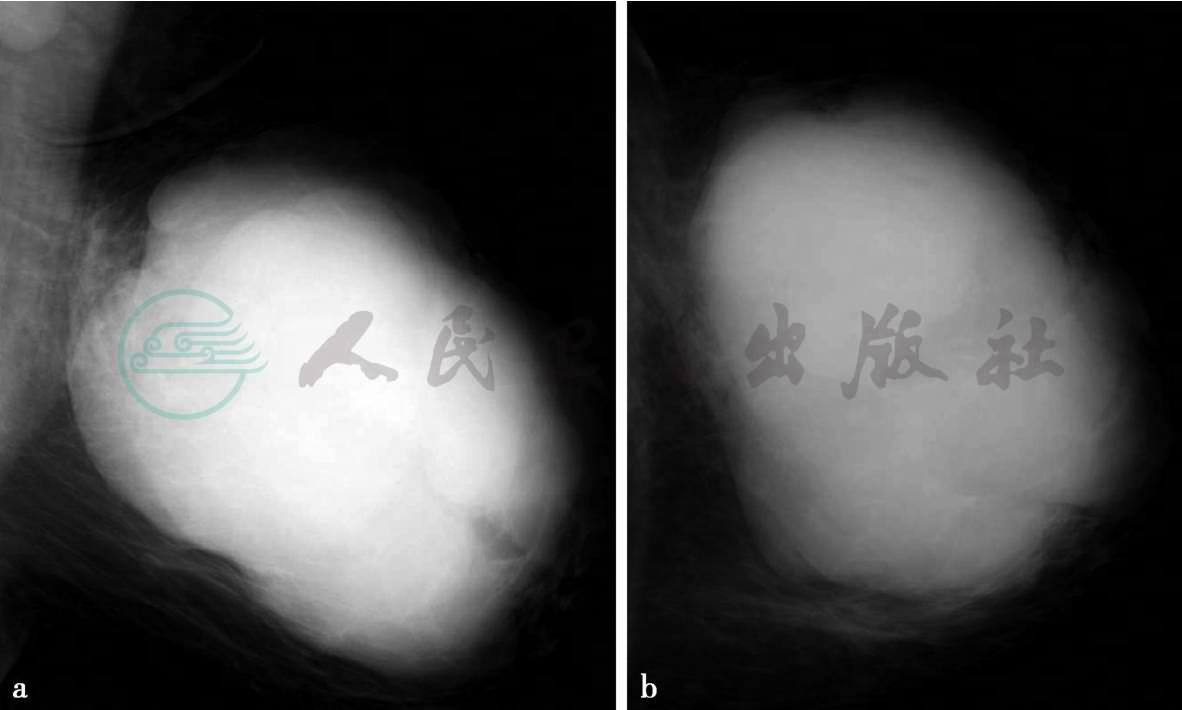

X线及MRI平扫、增强扫描

图3 图3a,X线影像内外斜位(MLO位),图3b,X线影像头尾位(CC位)。图3a,X线显示左乳巨大分叶状肿块,界清,密度增高且不均匀,未见恶性钙化,周围血管影增多,左腋区淋巴结增大。图3c~g,MRI检查。图3c,横断面T1加权成像,图3d,横断面T2加权成像,图3e,横断面增强压脂T1加权成像,图3f,ADC图,图3g,时间—信号强度曲线。MRI检查示左乳内巨大肿物,边界清,有完整包膜,分叶状,信号不均匀,内见囊状间隙(图d箭头所示)及低信号分隔(图e箭头所示),ADC值约0.83×10-3mm2/s,动态增强后囊状间隙及分隔无强化,时间—信号强度曲线呈流出型